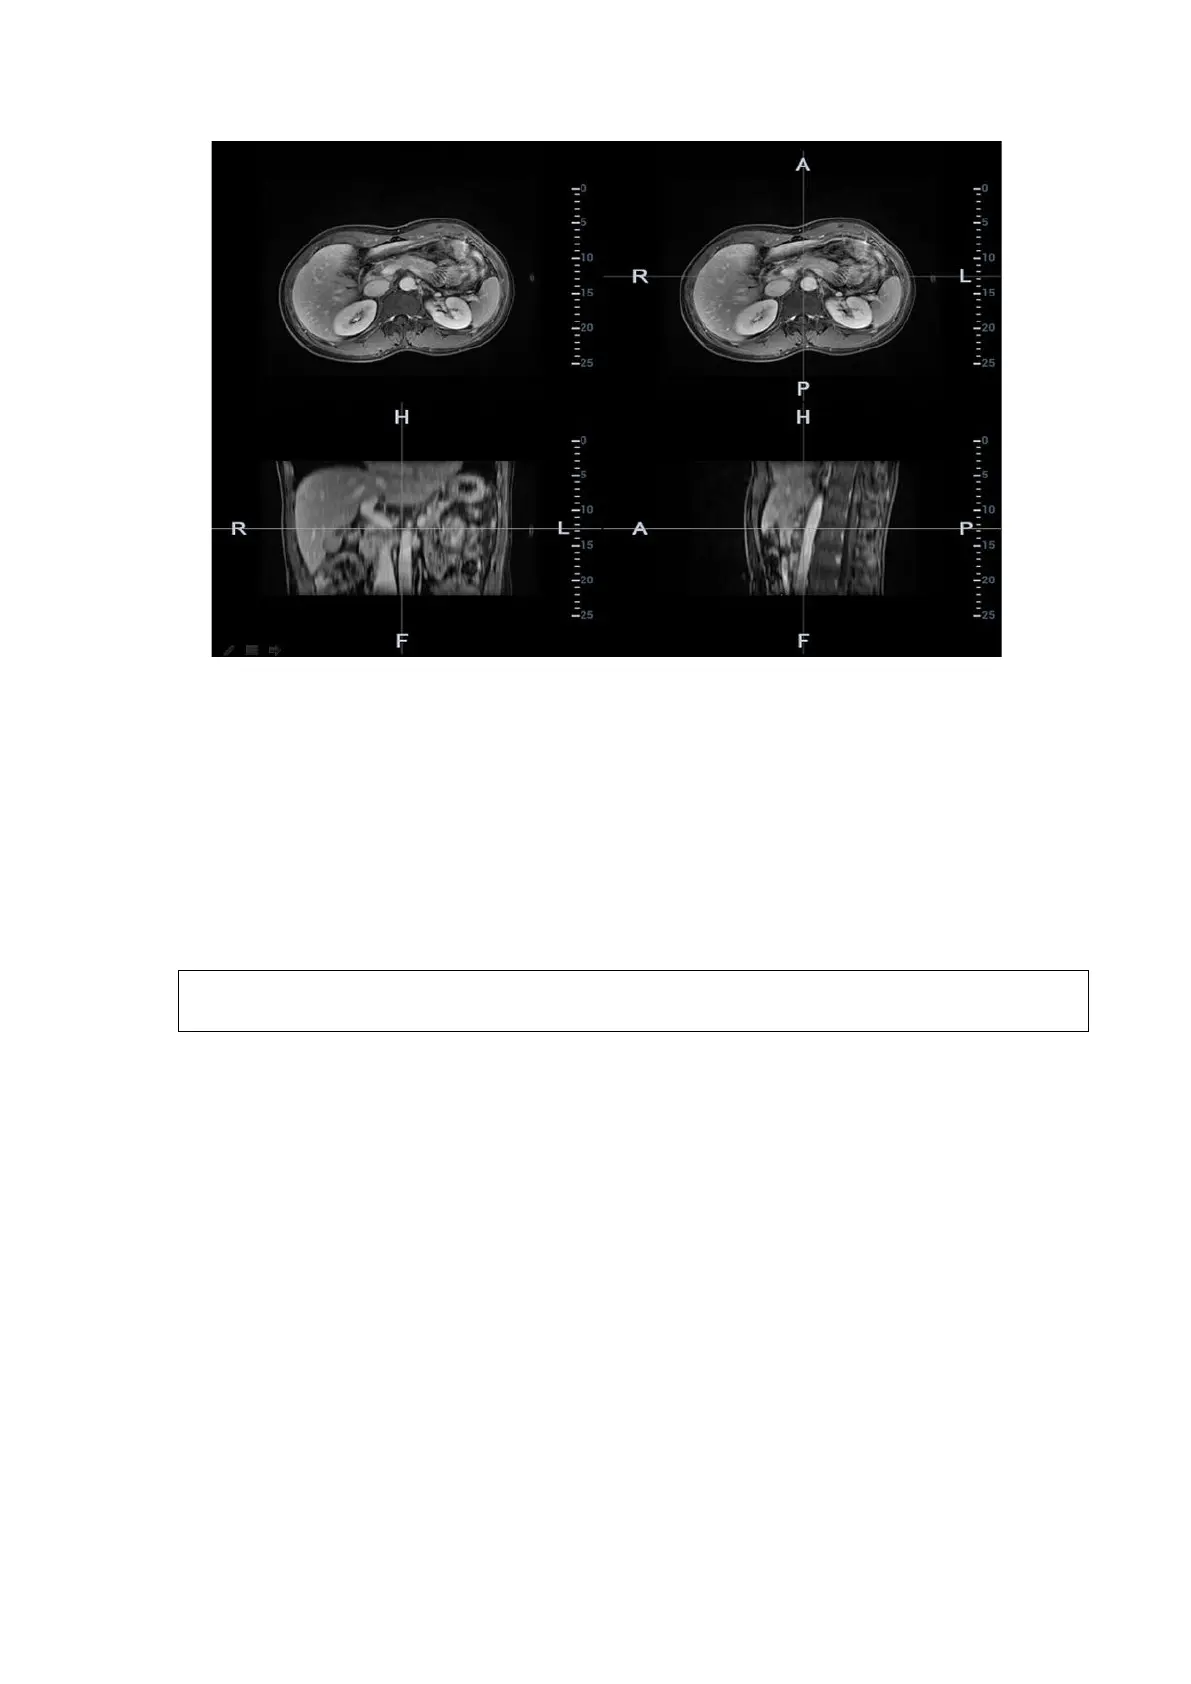

2. Press <Cursor> to show the cursor. Mark on the axial plane (top-right)/coronal plane (bottom-

left)/sagittal plane (bottom-right). The procedures to make marks are given below:

Select Manual tracing” or Circle tracingin the Mark” drop-down list.

Circle tracing: Press <Set> to locate the center at the core of the lesion. Roll the trackball to

adjust the radius. Envelop the tumor or the lesion with the circle. Double press <Set> to

complete adding the mark.

Manual tracing: roll the trackball to manually envelop the lesion. Rotate the <4D> key to scroll

the CT/MR/PET/Freehand image and continue to mark the lesions. After lesions of all the

desired CT/MR/PET/Freehand planes are marked, tap [Accept Slice Trace] to add marks.

Tips: At least two CT/MR/PET/Freehand planes should be marked when performing manual

tracing.

Note: The Ultrasound System adds 3-dimesnsional sphere mark to CT/MR/PET/Freehand

volume data. Set the target mark based on your sphere center and sphere radius.

Rotate [Ablative Margin] to add the ablative margin for this mark. See also Ablative Margin

description below.

Mark the tumor (a maximum of 20 tumors can be marked). The color of the mark can be

green, blue, or red in turn. These colors appear in circle. The sphere diameter and ablative

margin appear in the result window.